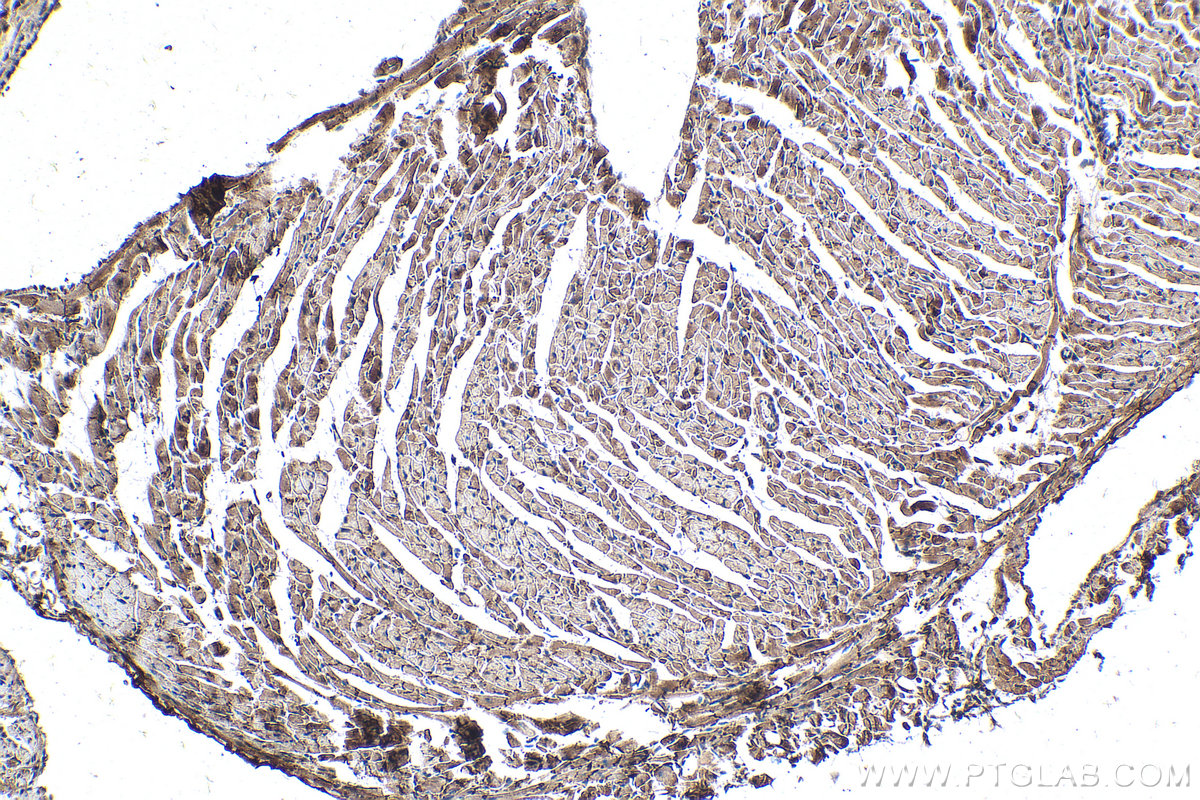

| Positive IHC detected in | human liver tissue, mouse heart tissue,  mouse testis tissue,  rat brain tissue,  rat testis tissue Note: suggested antigen retrieval with TE buffer pH 9.0; (*) Alternatively, antigen retrieval may be performed with citrate buffer pH 6.0  |

60177-1-Ig targets CKM-Specific in WB, IHC, IF-P, ELISA applications and shows reactivity with human, mouse, rat samples.

| 全称 | creatine kinase, muscle |

| 别名 | CKM, 2G3F6, Creatine kinase M-type, CPK-M, CKMM |

CKM, also named as CKMM and M-CK, is a member of the ATP:guanido phosphotransferase protein family. It is a cytoplasmic enzyme involved in energy homeostasis and is an important serum marker for myocardial infarction. CKM reversibly catalyzes the transfer of phosphate between ATP and various phosphogens such as creatine phosphate. It acts as a homodimer in striated muscle as well as in other tissues, and as a heterodimer with a similar brain isozyme in heart. CK isoenzymes play a central role in energy transduction in tissues with large, fluctuating energy demands, such as skeletal muscle, heart, brain and spermatozoa. CK MB consists of a dimer of nonidentical chains. With MM being the major form in skeletal muscle and myocardium, MB existing in myocardium. CKM has a calculated molecular mass of 43 kDa, and the 90-kDa and 130-kDa bands could be due to acovalent cross-linking of two and three CKm subunits, respectively (PMID: 20195383).